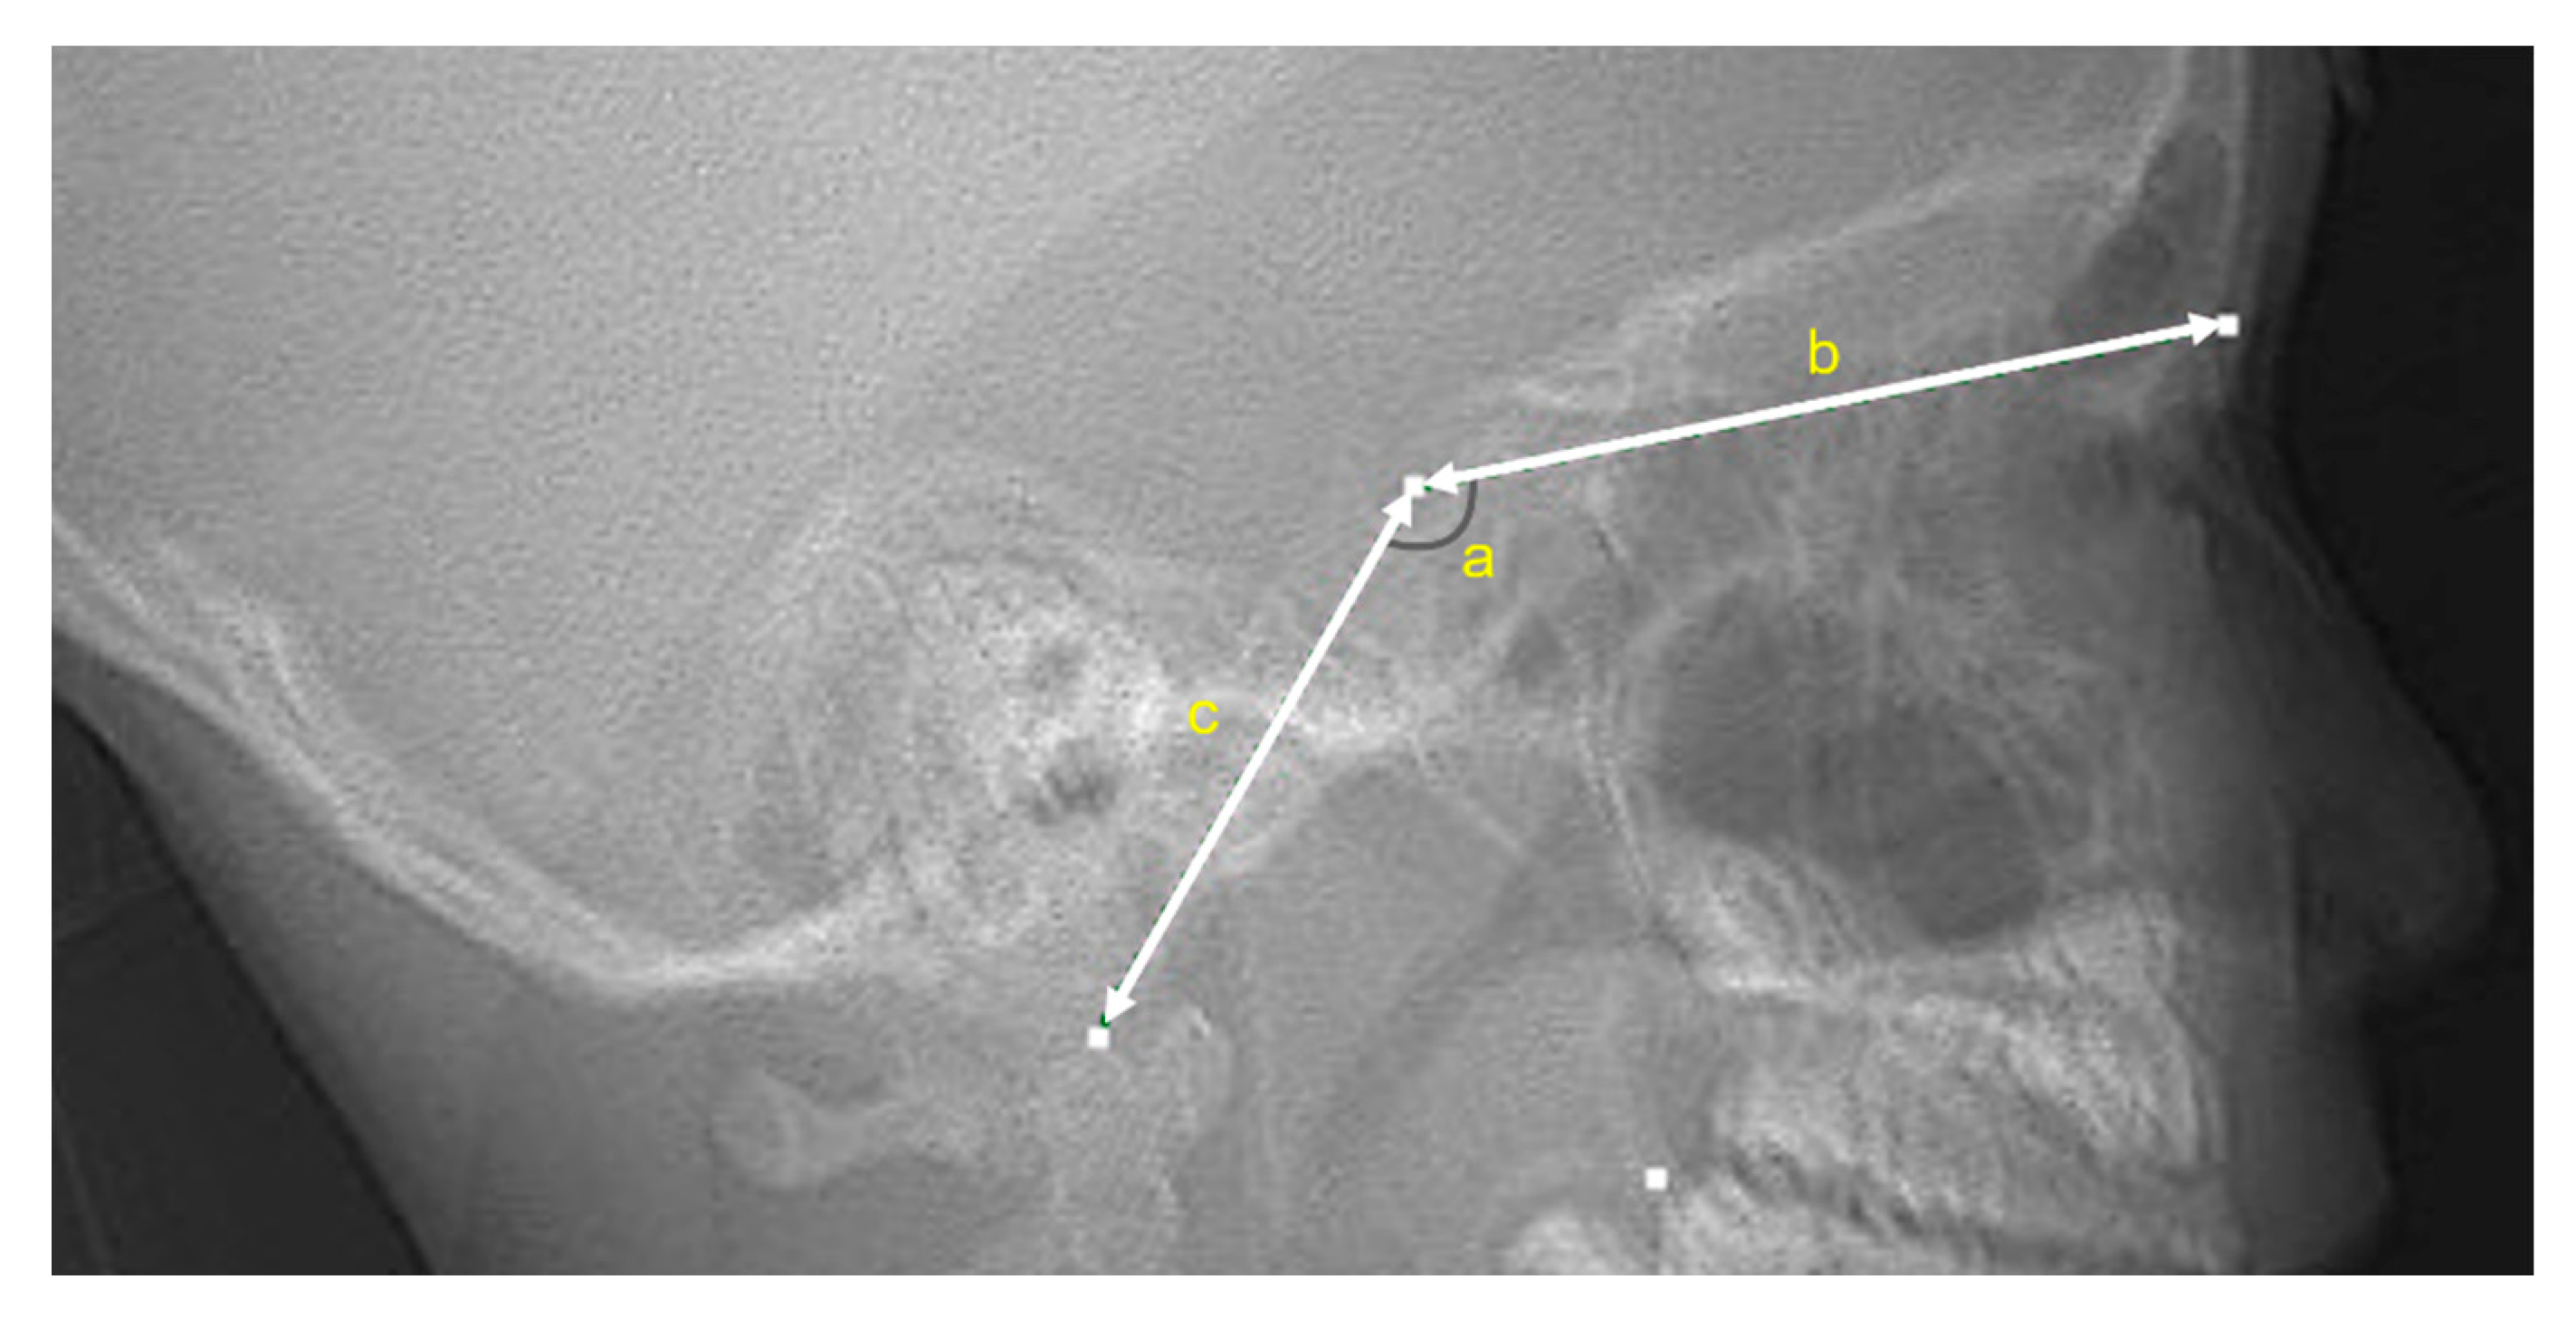

2.2. Three-Dimensional Computed Tomography

3.2. Volumetric and Dimensional Measurements of the Sphenoid Sinus According to Age and Its Relationship with the Cranial Base